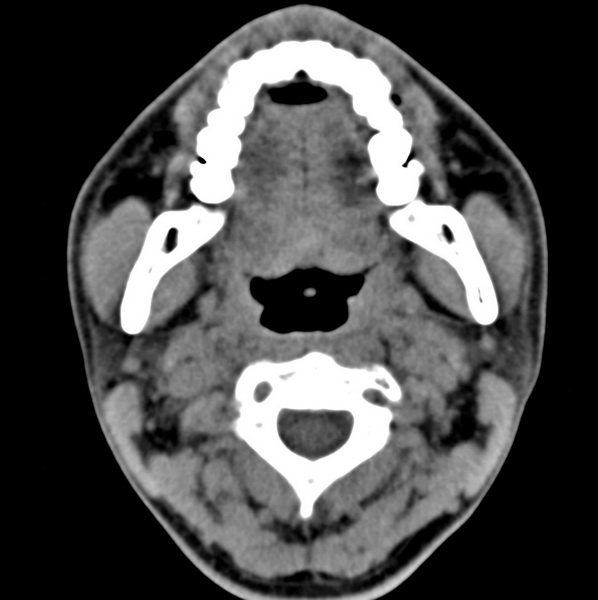

男、31、鼻咽部肿瘤放疗后请帮忙看看。

效果好,右侧破裂孔扩大,局部骨质缺损,为颅底骨质破坏。

1)鼻咽部肿瘤侵犯颅底放疗术后改变。2)左侧蝶窦炎。

咽后壁增厚,左侧咽鼓管隆突增大、咽鼓管咽口变浅,同侧咽旁间隙较窄。右侧颅底骨质破坏?为什么不在同一侧?

鼻咽部肿瘤侵犯颅底放疗术后改变.